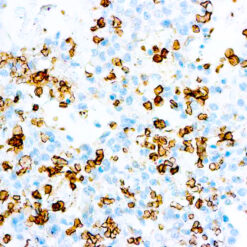

Prostate Specific Antigen, PSA

This product is intended for qualitative immunohistochemistry with normal and neoplastic formalin-fixed, paraffin-embedded tissue sections, to be viewed by light microscopy. Clinical interpretation of staining results should be accompanied by histological studies with proper controls. Patients’ clinical histories and other relevant diagnostic tests should be utilized by a qualified person(s) when evaluating and interpreting results.

| Immunogen | Prostate specific antigen isolated from human seminal plasma. |

| Positive Control Tissue | Prostate carcinoma |